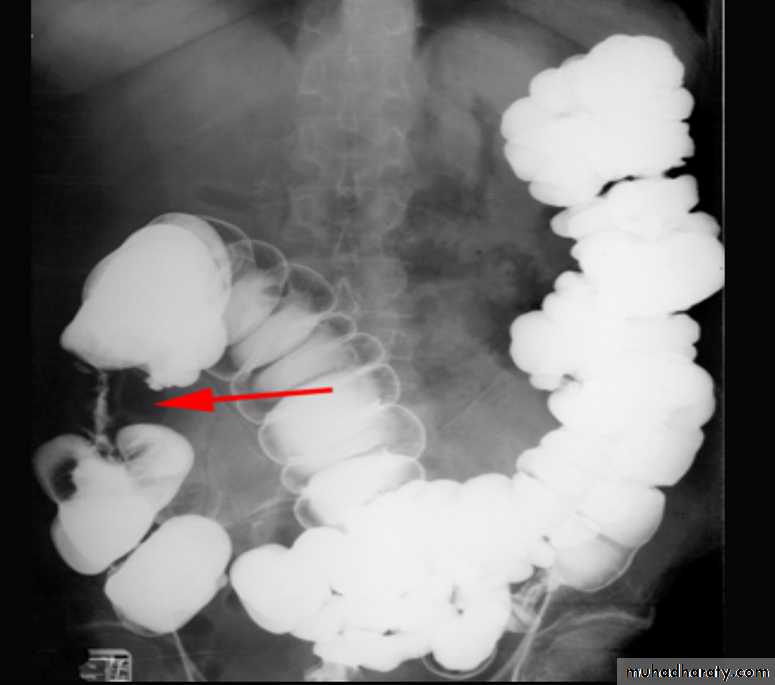

Ba enema

• Morphological types:• 1_ Ulcerative : give rise to irregularity of the colon with ulceration.

• 2_ Constrictive or infiltrative ( Annular ) type :

• a- Constant narrowing .

• b-Shouldering sign, apple core sign .

• c- Destruction of mucosa at narrow area .

• d- Double track due to fistula .

• e- In severe constriction ; stoppage of Ba. Flow with proximal dilatation .

3_Proliferative type : give rise to :

a- Large , constant filling defect with irregular margin .

b- Destruction of mucosa .

c- Intestinal obstruction

apple core lesion in the descending colon

Multiple lesions are seen in the liver and spleen consistent with metastases